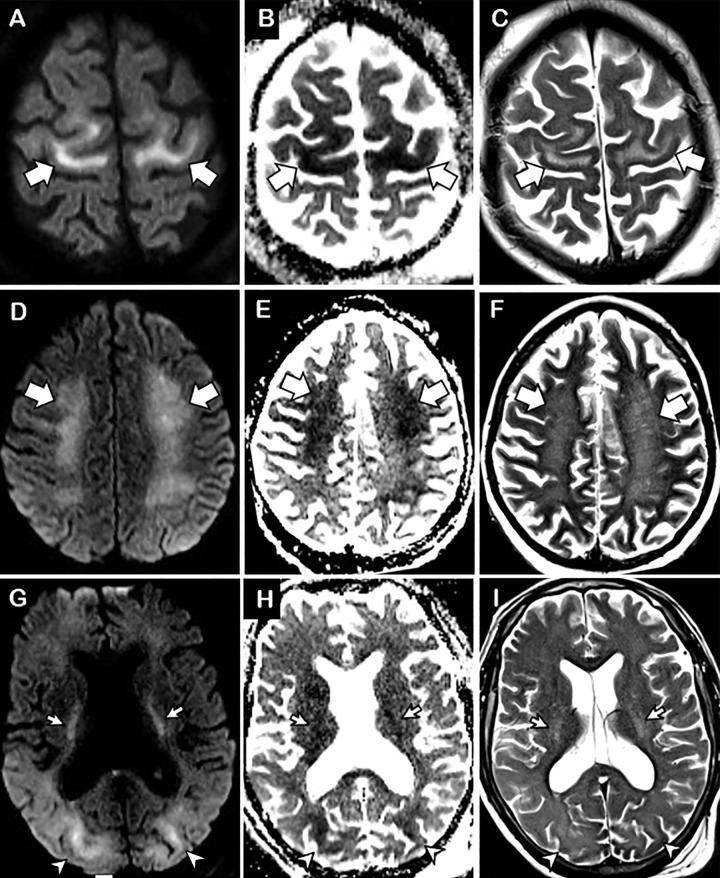

Diffuse leukoencephalopathy and juxtacortical and/or callosal microhemorrhages were brain imaging features in critically ill patients with coronavirus disease 2019. Coronavirus disease 2019 (COVID-19) has been reported in association with a variety of brain imaging findings such as ischemic infarct, hemorrhage, and acute hemorrhagic necrotizing encephalopathy. Herein, the authors report brain imaging features in 11 critically ill patients with COVID-19 with persistently diminished mental status who underwent MRI between April 5 and April 25, 2020. These imaging features include confluent T2 hyperintensity and mild restricted diffusion in bilateral supratentorial deep and subcortical white matter (in 10 of 11 patients) and multiple punctate microhemorrhages in juxtacortical and callosal white matter (in seven of 11 patients). The authors also discuss potential pathogeneses.

弥漫性脑白质病和皮质下及/或胼胝体微出血是 COVID-19 危重症患者的脑部影像学特征。有报道称,COVID-19(新冠肺炎)与多种脑部影像学表现相关,如缺血性梗死、出血和急性出血性坏死性脑病。在此,作者报告了 11 例 COVID-19 危重症患者的脑部影像学特征,这些患者的精神状态持续减退,于 2020 年 4 月 5 日至 4 月 25 日期间接受 MRI 检查。这些影像学特征包括 11 例患者中有 10 例双侧大脑半球深部和皮质下白质存在融合性 T2 高信号和轻度弥散受限,以及 7 例患者存在皮质下和胼胝体白质内多发性点状微出血。作者还讨论了潜在的发病机制。